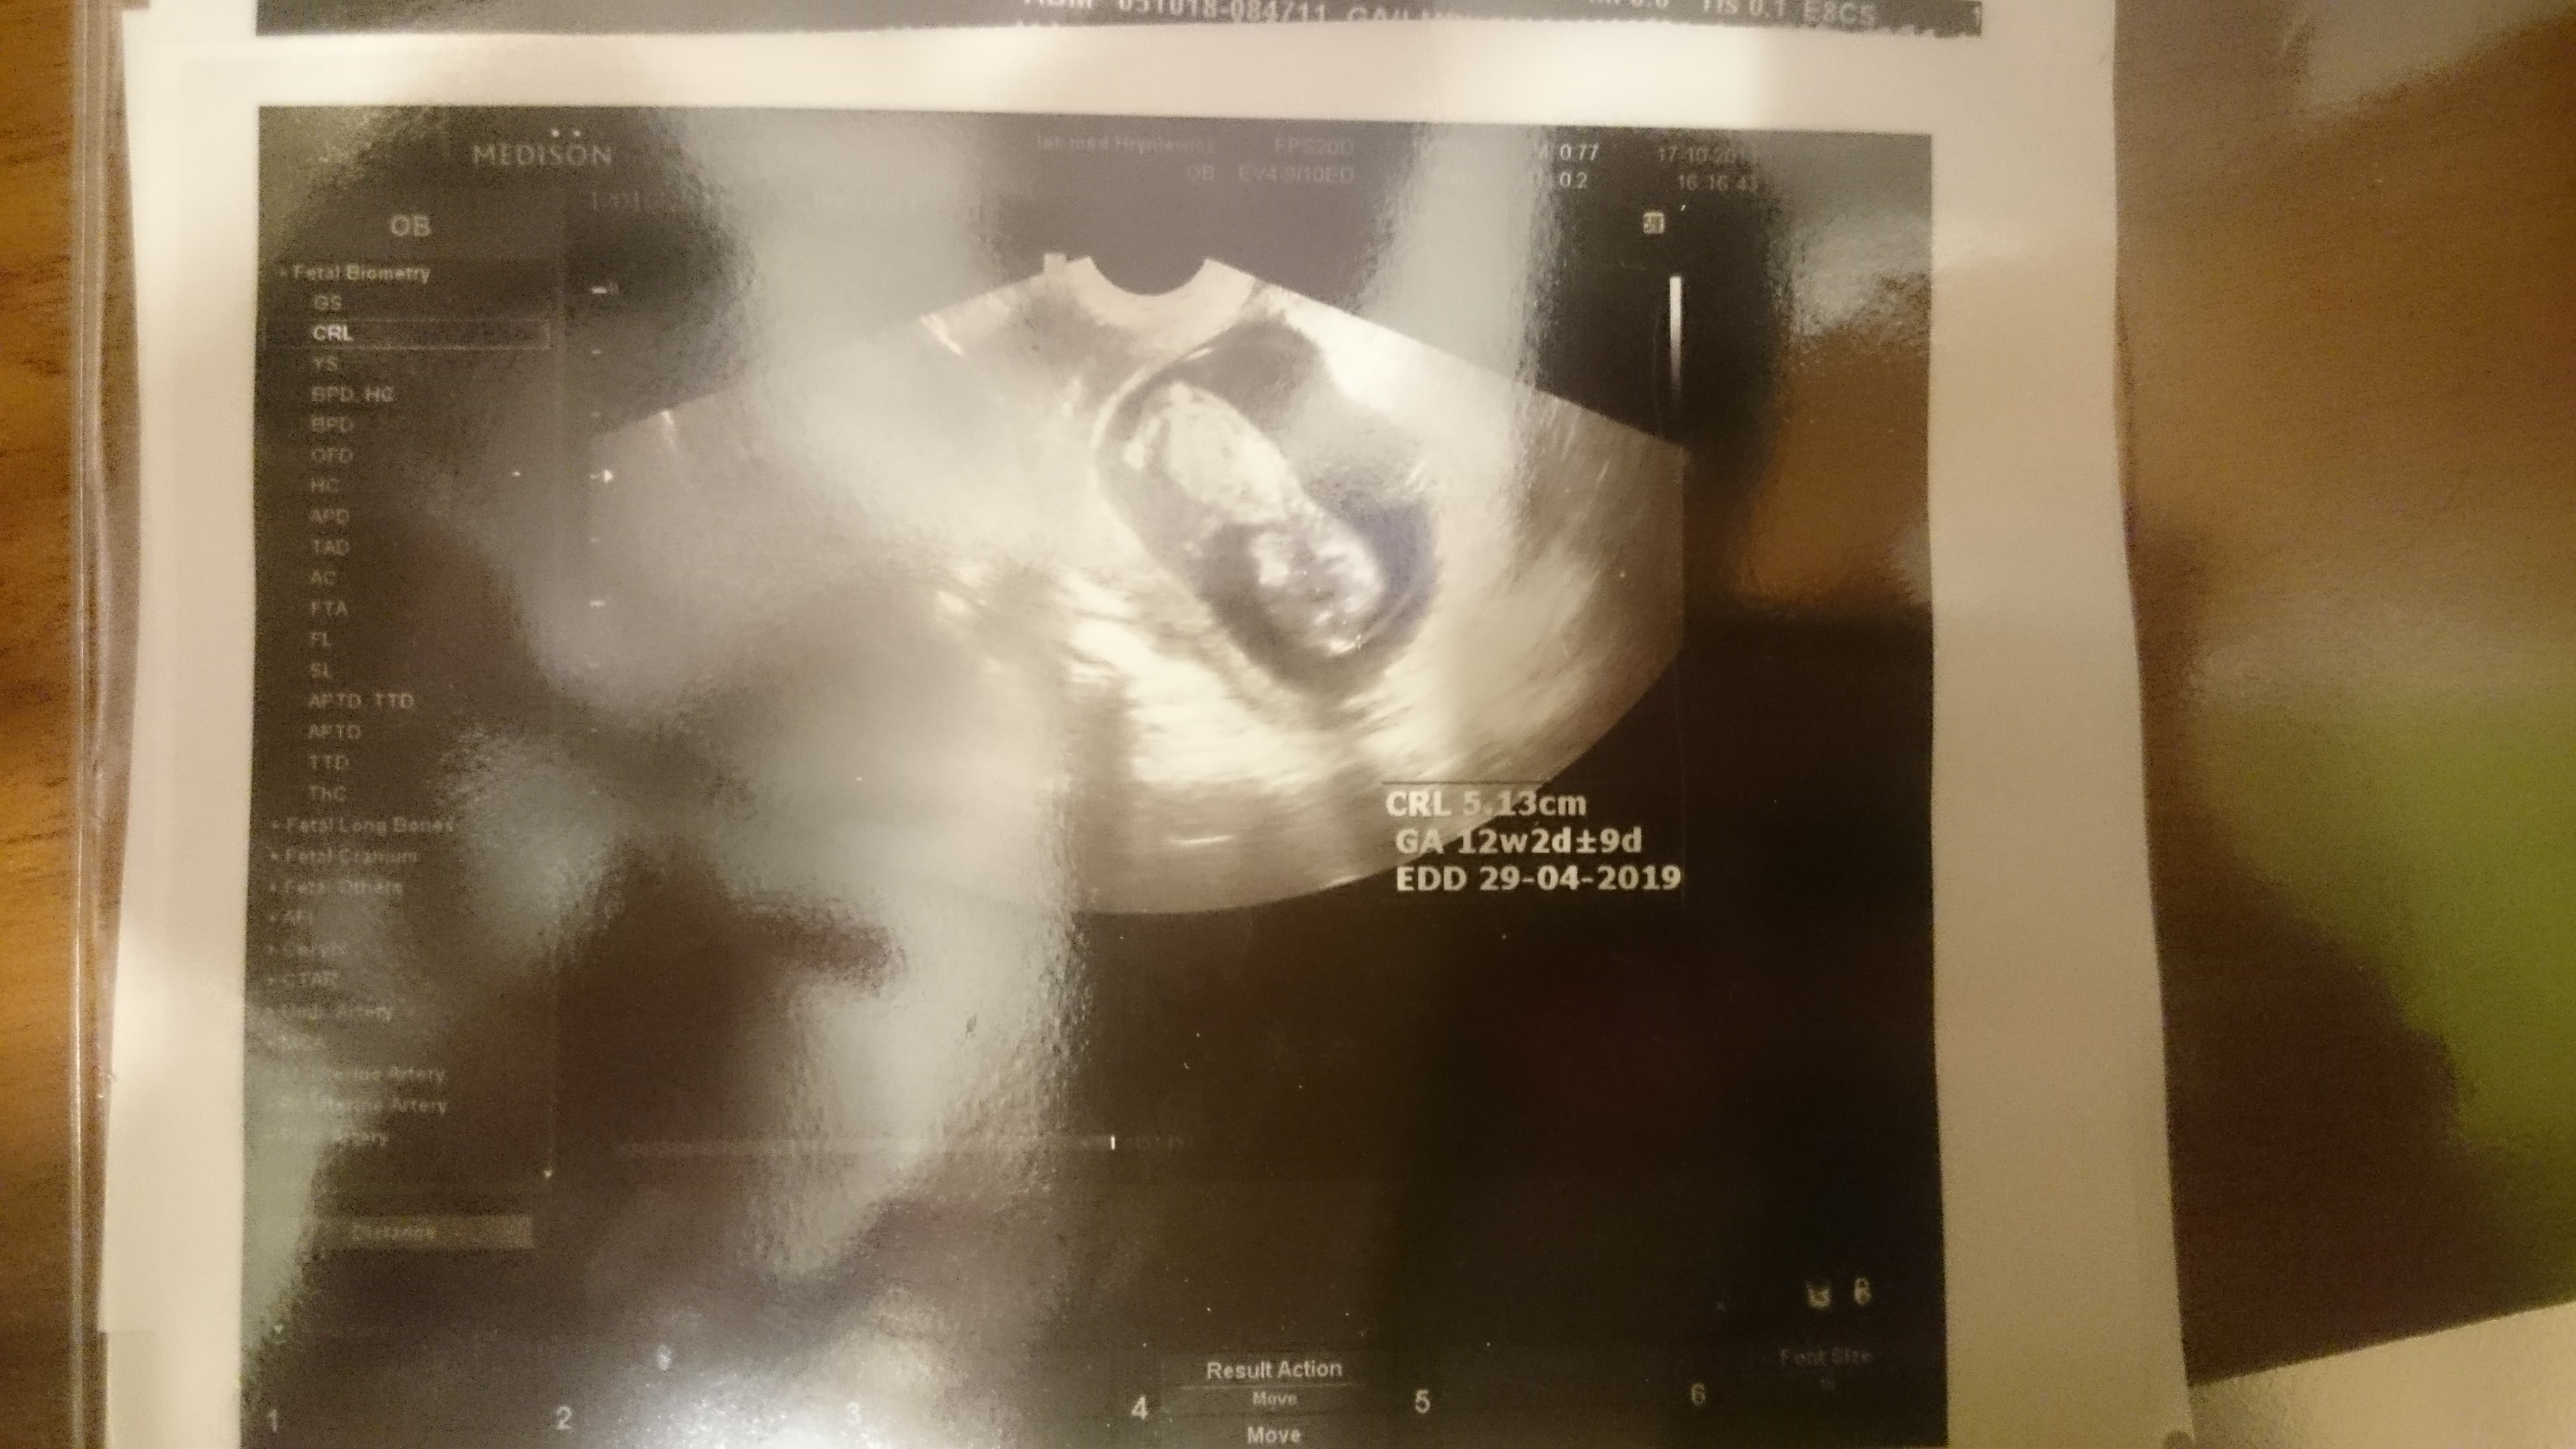

Dziewczyny, ja już św wizycie i jestem w szoku i nie wiem co mam wam napisać... Zacznę tak. Wg om 11+5, wg wielkości z poprzedniego usg powinno być 10+6 a na dzisiejszym usg wyszło 12+2!!!! Dzidziuś ma 51mm, kopie jak szalony! Termin mi się przesunął na 29.04. Jestem w totalnym szoku! Oczywiście już się zastanawiam czy to normalne... Ehh, cała ja. Serduszko pięknie bije, nie wiem ile na minutę ale na ucho równie pięknie jak poprzednio :) lekarka się śmieje że nie będę miała spokojnego dziecka :p powiedziała też że coś dużo tego między nogami, ale to jeszcze za wcześnie żeby mówić czy ma rację ;)

A tu mój lobuziak mały ;)